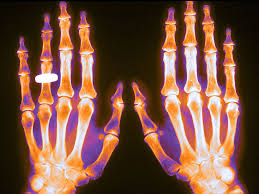

Evalúe los factores individuales de un paciente en cuanto a beneficios y riesgos antes de iniciar el tratamiento con denosumab 60 mg, especialmente en aquellos con fractura vertebral previa. Los pacientes no deben interrumpir el tratamiento con denosumab sin la revisión de un especialista. Drug Safety Update, 26 de Agosto de 2020

Denosumab: efecto rebote y otros efectos indeseados graves

Butlletí Groc vol.31 núm.3 jul-set 2018 El denosumab es un anticuerpo monoclonal que inhibe la resorción ósea producida por los osteoclastos. Fue comercializado en 2010 para el tratamiento de la osteoporosis. En estos años se han identificado varios efectos adversos potencialmente graves: predisposición a infecciones, cáncer, reacciones de hipersensibilidad, trastornos autoinmunes, e incremento de la incidencia de múltiples fracturas vertebrales espontáneas al suspender el tratamiento. En este número revisamos estas novedades.